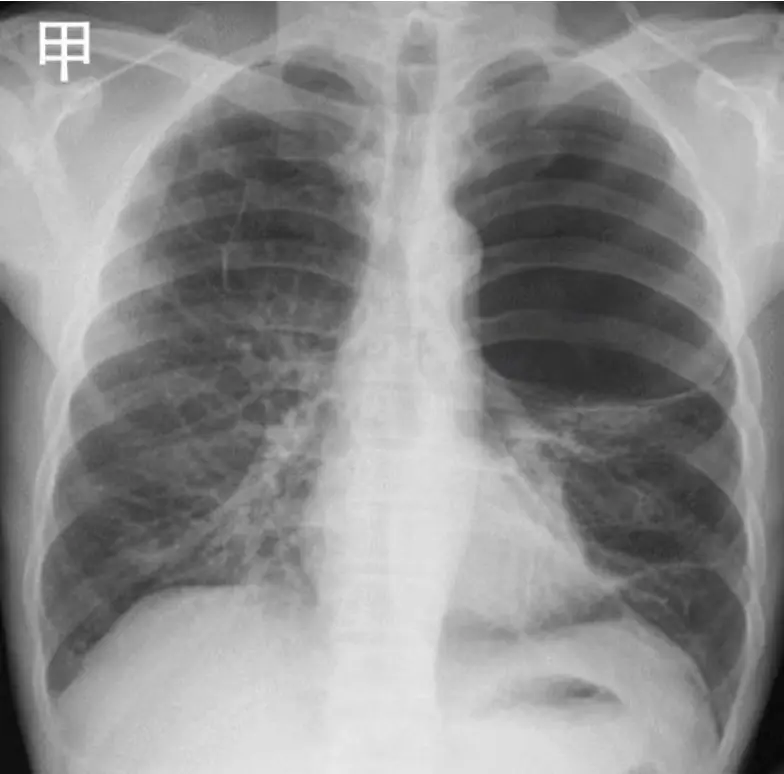

甲、乙兩位病人都主訴呼吸喘及左胸不適,胸部 X 光檢查如圖 (九)。關於是否適合進行左胸胸管引流做為緩解病人症狀的處置決策,下列何者最適當?

- 甲:左上肺野可見大片透亮區域,邊緣內緣有薄壁狀結構,佔據左上肺超過三分之一,肺泡紋理在其餘肺野維持可見,心膈線及縱隔未顯著偏移,符合giant pulmonary bulla的表現。

- 選項A(甲、乙皆適合):錯誤。甲為肺實質內巨大肺泡,非胸膜腔積氣;乙為肺不張,非需胸管處理之胸膜腔病變。

- 選項B(甲適合、乙不適合):錯誤。甲不符胸管適應症。

- 選項C(甲不適合、乙適合):錯誤。乙為肺不張,胸管無助恢復肺擴張。

- 選項D(甲、乙皆不適合):正確。兩者病變均不在胸膜腔中,無法藉胸管緩解。

甲例為giant pulmona